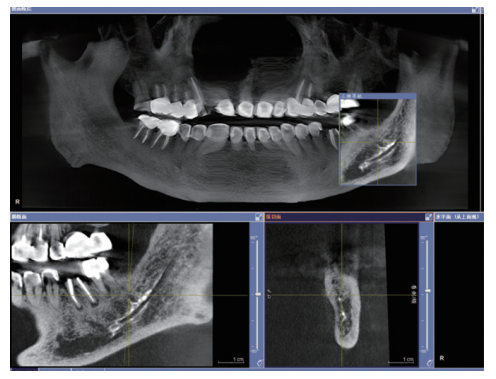

影像学检查:CBCT矢状面、冠状面示37根充糊剂进入下颌管患者。

CBCT示37根充糊剂进入下颌管

CBCT矢状面、冠状面示37根充糊剂进入下颌管

可见37冠部修复,根管内有高密度充填物影像,远中根管充填物沿伸至根尖周并进入左下颌管内,下颌管内有条状高密度影(近中至36远中根下颌管处,远中至下颌升支1/3处);初诊锥形束CT(CBCT)显示37根管内见高密度充填物影像,根尖周未见密度减低影,疑似大量充填糊剂沿37远中根进入下颌管内,并包绕于管壁。较5年前曲面体层片无明显变化。